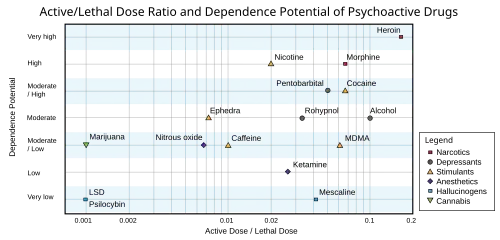

According to Delphic analysis by British researchers in 2007, cannabis has a lower risk factor for dependence compared to both nicotine and alcohol.[109] However, everyday use of cannabis may be correlated with psychological withdrawal symptoms, such as irritability or insomnia,[105] and susceptibility to a panic attack may increase as levels of THC metabolites rise.[110][111] Cannabis withdrawal symptoms are typically mild and are not life-threatening.[112] Risk of adverse outcomes from cannabis use may be reduced by implementation of evidence-based education and intervention tools communicated to the public with practical regulation measures.[113]

- ^ "Drug Toxicity". Web.cgu.edu. Archived from the original on 25 March 2008. Retrieved 17 February 2011.